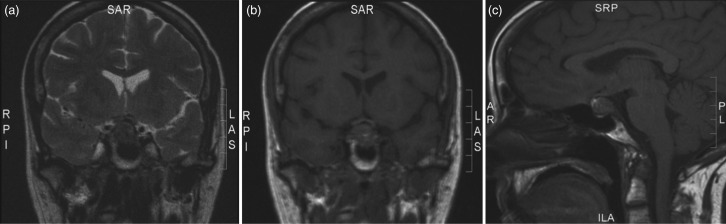

Unlabelled: Metastases to the pituitary gland are an uncommon complication of thyroid cancer. They resemble pituitary neoplasms posing a diagnostic challenge. We present a case of an aggressive non-radioiodine avid papillary thyroid cancer with recurrent pituitary metastases and a review of the literature. A 70-year-old woman with a history of papillary thyroid cancer and bony metastases presented with symptoms of hypoadrenalism and peripheral vision loss. Magnetic resonance imaging showed a large pituitary mass impinging on the optic chiasm. She underwent transsphenoidal resection followed by (131)I ablation. Post-therapy scintigraphy showed no iodine uptake in the sellar region or bony metastases. Histology of the pituitary mass confirmed metastatic papillary thyroid cancer. Fifteen months later, she had a recurrence of pituitary metastases affecting her vision. This was resected and followed with external beam radiotherapy. Over 2 years, the pituitary metastases increased in size and required two further operations. Radioactive iodine was not considered due to poor response in the past. Progressively, she developed a left-sided III and IV cranial nerve palsy and permanent bitemporal hemianopia. There was a rapid decline in the patient's health with further imaging revealing new lung and bony metastases, and she eventually died 8 months later. To our knowledge, this is the first case of pituitary metastases from a radioiodine-resistant papillary thyroid cancer. Radioiodine-resistant metastatic thyroid cancer may exhibit rapid aggressive growth and remain poorly responsive to the currently available treatment.

Learning points: Differentiated thyroid cancer (DTC) has an excellent prognosis with <5% of the cases presenting with distant metastases, usually to lung and bone.Metastasis to the pituitary is a rare complication of DTC.The diagnosis of pituitary insufficiency secondary to pituitary metastases from DTC may be delayed due to the non-specific systemic symptoms of underlying malignancy and TSH suppression therapy for thyroid cancer.The imaging characteristics of metastases to the pituitary may be similar to non-functioning pituitary adenoma.Radioiodine refractory metastatic thyroid cancer has significantly lower survival rates compared with radioactive iodine-avid metastases due to limited therapeutic options.